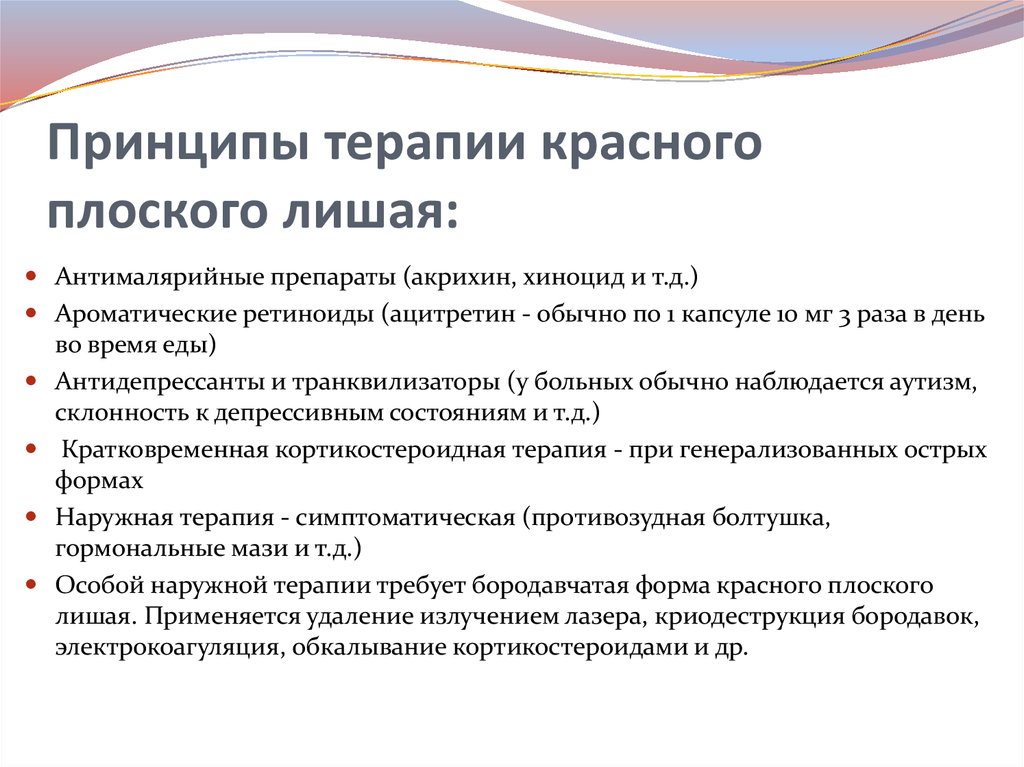

Фото Красного Плоского

Фото Красного Плоского 103 фото